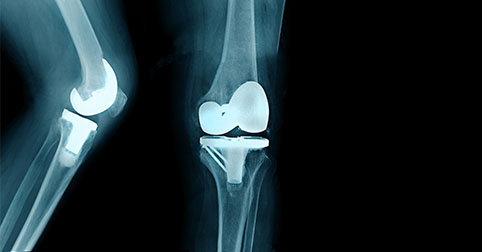

Αρθροπλαστική γόνατος: Ποια αθλήματα επιτρέπονται και μετά από πόσο χρονικόδιάστημα είναι ασφαλής η επιστροφή;

Ασθενείς που έχουν υποβληθεί σε ολική αρθροπλαστική γόνατος και έχουν αναρρώσει, έχουν τη δυνατότητα να συνεχίσουν, υπό προϋποθέσεις, τις αθλητικές τους δραστηριότητες.

Η ολική αρθροπλαστική γόνατος αποτελεί τη μοναδική οριστική θεραπεία της οστεοαρθρίτιδας τελικού σταδίου. Τα τελευταία χρόνια και σε σχέση με ασθενείς που κληθήκαμε να χειρουργήσουμε στο παρελθόν, οι ασθενείς που υποβάλλονται σε αρθροπλαστική γόνατος είναι πλέον νεότεροι, ή αν είναι ηλικιωμένοι,είναι αρκετά δραστήριοι.Υπάρχουν πολλοί παράγοντες πουσυντελούν στο γεγονός ότι νεότερες ηλικίες αποφασίζουν να προχωρήσουν σε αρθροπλαστική γόνατος.Αρχικά,τα υψηλά ποσοστά παχυσαρκίας, μια από τις αιτίες καταστροφής του χόνδρου. Επίσης, η ένταξη της συστηματικής άσκησης στη ζωή του πληθυσμού, η οποία ναι μεν προάγειτην καλή υγεία, αλλά παράλληλα αυξάνει τον κίνδυνο για μετατραυματικές αρθρίτιδες. Τέλος, τα καλά αποτελέσματα του χειρουργείου, τα οποία ενθαρρύνουν όλο και περισσότερους ασθενείς να αναζητήσουν από νωρίς τη λύση για τιςενοχλήσεις που αντιμετωπίζουν στο γόνατο.Με τον τρόπο αυτό, έχουν τη δυνατότητα να επιστρέφουν όσο το δυνατόν νωρίτερα στις δραστηριότητες τους, να μην αντιμετωπίζουν πλέον δυσκολία και πόνο, να μπορούν να συμμετέχουν σε αθλήματα, να συνεχίζουν να μεγαλώνουν χωρίς λειτουργικά προβλήματα και να κατακτούν καθημερινά τους στόχους που θέτουν, διατηρώντας και τονώνοντας την αυτοπεποίθησή τους.